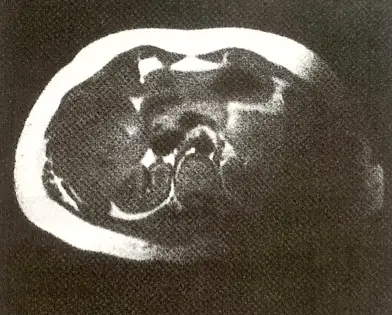

下圖磁振造影所示的右半側影像,其造成的原因與敘述,下列何者正確?

本題提供一張腹部之軸切面 MRI 影像。觀察影像可發現,左半側(病人右側)具備正常的解剖結構、組織訊號與對比;然而,影像右半側(病人左側)卻出現大範圍且嚴重的訊號缺失(Signal drop-off 或 Shading),該區域幾乎呈現全黑。 值得注意的是,此訊號缺失區域並未伴隨明顯的幾何扭曲(Geometric distortion)。這種單側大面積平滑的訊號衰減,最常見的成因為「表面線圈(Surface coil)」的某個陣列元件損壞、未正確連接(未插妥),或是射頻脈衝(B1 場)極度不均勻所導致的表面線圈輪廓假影或 RF shading。

- (A) 此不均勻的影像是一種鐵磁性( paramagnetic )假影:錯誤。首先,金屬等高磁化率物質造成的假影通常會表現為局部的訊號空洞(Signal void),並伴隨明顯的空間幾何扭曲(Blooming artifact),不會呈現如圖中這般大範圍且平滑的單側訊號消失。此外,選項在專有名詞配對上存在錯誤,鐵磁性應為 Ferromagnetic,而 Paramagnetic 為順磁性。